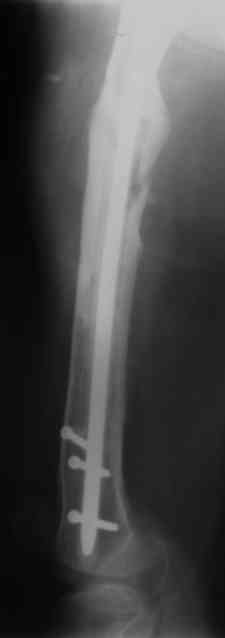

Вчера наш пациент был на контрольном осмотре. Вроде все идет нормально. Рентгенограммы от 25 сентября 2007 г. (прошло 5 месяцев после операции) прилагаю.